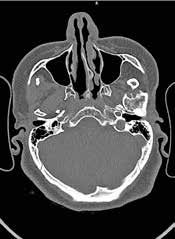

A las 36 horas de vida presenta nuevo empeoramiento respiratorio, se solicita estudio completo y se realiza punción lumbar (a pesar de paráme tros infecciosos negativos en la analítica). Se obtiene líquido purulento y se procede a escalada de tratamiento a ceftriaxona y ampicilina (mantiene tratamiento durante 7 y 3 días respectivamente, no aislándose microorga nismos en muestras de líquido cefalorraquídeo ni hemocultivos). Se repite la radiografía de tórax en la que se evidencia neumotórax de nueva apa rición e imagen sugestiva de neumomediastino. Ante estos hallazgos, se solicita TC de tórax que confirma el diagnóstico y descarta la existencia de causas desencadenantes (Figura 2). Se mantienen requerimientos de VMNI durante 4 días más, siendo finalmente posible la desescalada gradual a oxigenoterapia con gafas nasales durante 4 días. Se consigue retirada del soporte respiratorio de manera completa pasados 8 días, realizando un control con TC de tórax a los 9 días de vida (Figura 3) que muestra mejoría significativa acompañándose de una recuperación clínica completa.

Figura 2. (Izq.) radiografía de tórax en proyección AP a las 36 horas de vida donde se objetiva neumotórax de nueva aparición (flechas azules) y una zona de hiperclaridad alrededor de la silueta cardíaca que sugiere importante neumomediastino (estrellas amarillas). (Der.) TC de tórax sin contraste intravenoso en ventana de pulmón que confirma la presencia de neumomediastino (estrella amarilla). Se objetivan focos de consolidación periféricos y bandas lineales de densidad aire paralelas y adyacentes a las vainas broncovasculares (flechas amarillas).